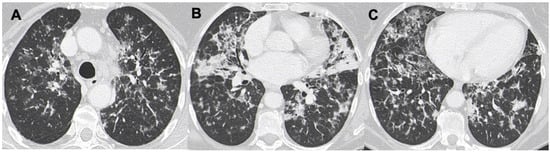

3.3. Ground-Glass Opacities

3.4. Interstitial Involvement

| LIP | Air-filled cysts, “halo sign”, masses and nodules with centrilobular appearance, GGO, patchy interstitial involvement | Infections, metastasis, neoplasm, MALT, sarcoidosis, amiloidosis |

| NHL | Nodule (usually single) < 2 cm; less frequently mass or consolidation, air bronchogram± | Infections, neoplasm, metastasis, MALT |